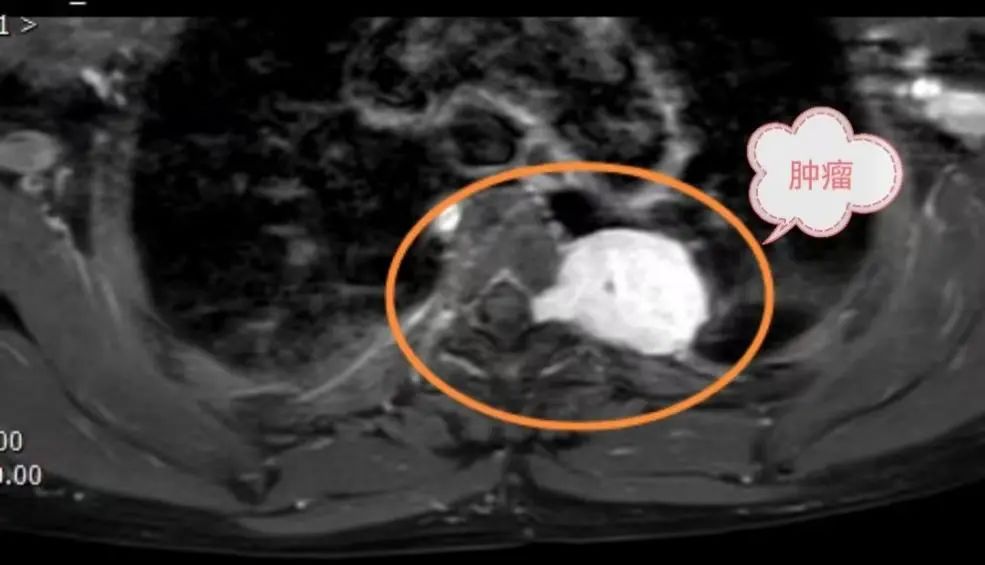

圖為:術(shù)前磁共振提示后縱隔腫瘤經(jīng)椎間孔侵入椎管

患者因后縱隔腫瘤經(jīng)椎間孔長入椎管,病情少見且有很高的手術(shù)風(fēng)險(xiǎn)——椎間孔內(nèi)腫瘤壓迫脊髓神經(jīng)可能致癱,完整切除腫瘤才能最大限度去除病變并降低術(shù)后復(fù)發(fā)。然而由于腫瘤植根于椎間孔并向椎管內(nèi)生長,稍有不慎就會造成難以控制的髓腔內(nèi)出血,嚴(yán)重的會造成截癱甚至危機(jī)生命,國內(nèi)外此類情況均有報(bào)道。

后縱隔神經(jīng)源性腫瘤多源于脊柱旁神經(jīng)組織,若沿椎間孔侵入椎管,則形成“啞鈴型腫瘤”,兩端膨大壓迫脊髓和周圍結(jié)構(gòu)。